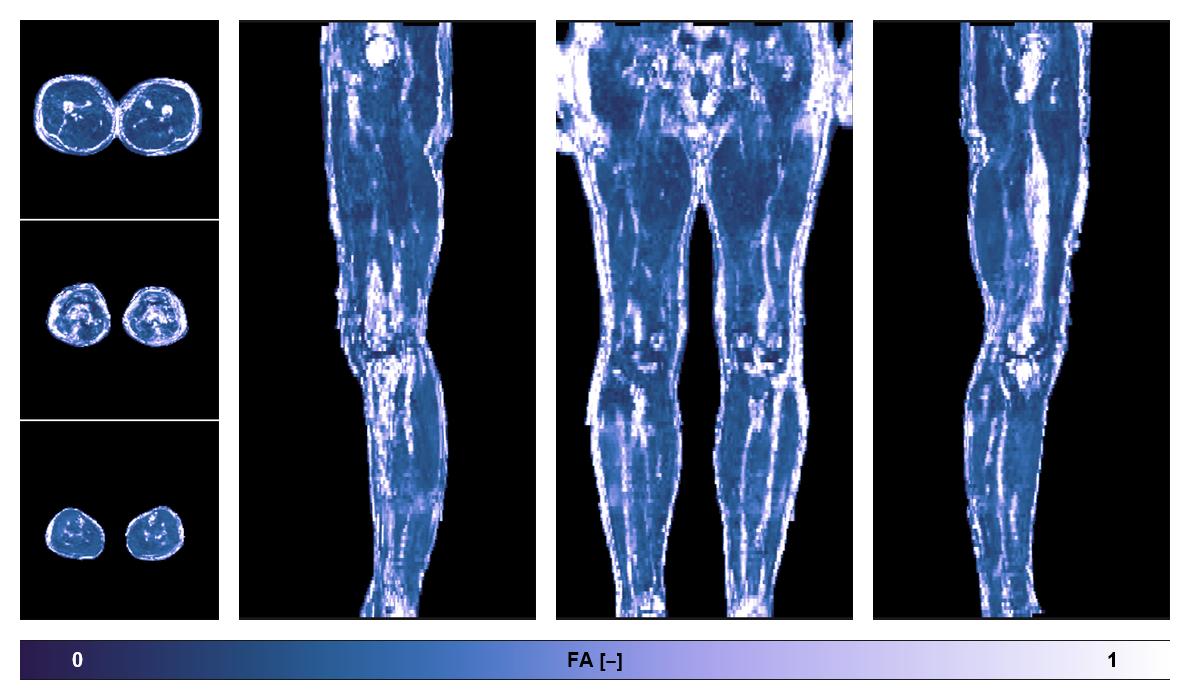

• Fractional anisotropy

IVIM corrected whole leg muscle fractional anisotropy obtained from diffusion tensor imaging.